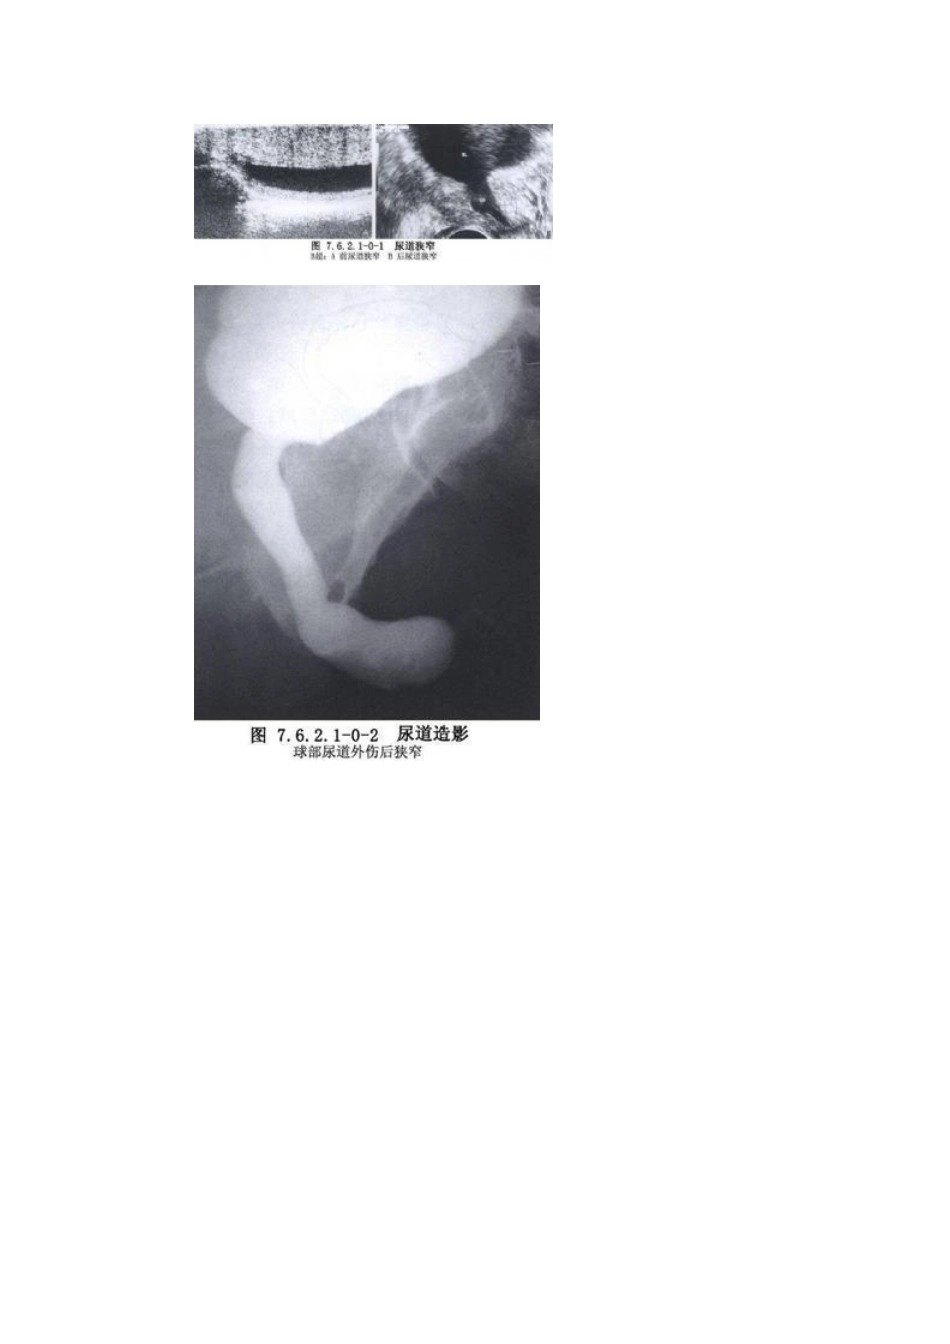

目录1.手术名称2.别名3.分类4.ICD编码5.概述6.适应症7.禁忌症8.术前准备9.麻醉和体位10.手术步骤1.1.探子插入尿道2.2.探子送入球部尿道3.3.探子尖端跨过膜部尿道4.4.探子尖端进入膀胱11.术中注意要点12.术后处理13.述评14.相关文献[返回]手术名称尿道狭窄扩张术[返回]别名尿道扩张术;dilatationoftheurethra[返回]分类泌尿外科/男性尿道手术/尿道狭窄的手术治疗[返回]ICD编码58.601[返回]概述男性尿道狭窄是泌尿外科常见病,按其病因可分为先天性、炎症性和外伤性3类。先天性尿道狭窄较少见,如先天性尿道外口狭窄、尿道瓣膜、精阜肥大、尿道管腔缩窄等。炎症性尿道狭窄由特异性或非特异性尿道感染所致。特异性感染中,以淋病性尿道狭窄较常见;非特异性感染中,因反复包皮、阴茎头炎症所致的尿道外口及阴茎部尿道狭窄常见,因留置导尿管不当所致的炎症性尿道狭窄已引起广泛重视,这类狭窄多见于海绵体部尿道,范围较广;外伤性尿道狭窄(traumaticurethralstricture)是最常见的后天性尿道狭窄,狭窄部位依损伤部位而定,会阴跨骑伤所致者多在球部尿道。骨盆骨折所致者,位于膜部或前列腺尖端尿道,一般狭窄段不长,但瘢痕较坚硬(图7.6.2.1-0-1~7.6.2.1-0-3)。严重的尿道狭窄可致上尿路积水和肾功能损害,在尿道狭窄部的近端及周围组织中常有炎症存在,有些病例可并发尿道周围炎、尿道周围脓肿,甚至向阴囊会阴部穿破,形成经久不愈的尿道瘘,亦常并发尿路及生殖道感染,有的病例还带有耻骨上膀胱造口,应根据具体情况做好术前准备工作。狭窄较轻、瘢痕不重者,可望通过尿道扩张术治愈。如尿道扩张术失败或疗效不佳,应选择其他手术治疗方法。腔内手术治疗尿道狭窄具有肯定的疗效,现已广泛应用于临床,具有创伤小、出血少、术后并发症少等优点,应作为治疗尿道狭窄的首选方法。但它需要特殊器械,对于复杂性尿道狭窄特别是狭窄段过长者,开放性手术治疗仍为主要手段。故腔内治疗尚不能完全取代其他手术疗法。[返回]适应症尿道狭窄扩张术适用于:尿道扩张术的主要适应证是预防和治疗炎症性、外伤性及尿道手术后的尿道狭窄。尿道扩张术治疗尿道狭窄,一方面是起到对狭窄部位的机械扩张作用,另一方面起到按摩作用,增进局部血液循环,促进瘢痕软化和浸润吸收。此外,尿道扩张术还可作为治疗慢性前列腺炎、慢性尿道炎、轻度膀胱颈梗阻等疾病的措施之一,并有探测尿道或膀胱内有无结石或金属性异物的作用。[返回]禁忌症1.急性尿道炎、急性前列腺炎,忌行尿道扩张术,以免炎症扩散。2.慢性尿道炎有较多的脓性分泌物者,忌行尿道扩张术。3.尿道损伤忌行尿道扩张术,以免加重损伤、出血、休克,或造成假道。4.疑有尿道肿瘤者。5.每次尿道扩张术后均有尿道热者。[返回]术前准备1.检查各号尿道探子是否齐备完整。一般来讲,应具有一套完整的尿道探子,以便于扩张尿道时按病情需要选择应用。准备导尿管,必要时供术后导尿用。2.有慢性尿道炎者,术前1~2d给予抗菌药物,并多饮水。[返回]麻醉和体位在门诊,多数病人或反复接受过尿道扩张术者,可在无麻醉下进行。对于较敏感者或初次行尿道扩张术者,可于术前15~30min给予镇静剂,或施以尿道表面麻醉。女性病人可用细棉签蘸以4%丁卡因轻轻插入尿道,留置5min后可产生麻醉效果。男病人可用2%利多卡因(lidocaine),5%哌罗卡因(metycaine),或5%普鲁卡因(procaine)10ml,灌注于尿道内,约5min即可产生表面麻醉效果。市售润滑止痛胶,不但有麻醉作用,而且具有润滑作用,使用更为方便。灌注压力宜低,以免因高压使药液经尿道粘膜下大量进入血循环而中毒。禁忌以可卡因尿道内灌注作表面麻醉。对于局部病变比较复杂,尿道狭窄比较严重,或需同时经耻骨上膀胱造口行尿道会师扩张者,最好在低位椎管内麻醉下进行。小儿可在静脉麻醉(硫喷妥钠),吸入麻醉或肌注氯胺酮入睡后施行。体位取平卧位,两腿稍分开,或截石位。[返回]手术步骤1.探子插入尿道若病人为平卧位,术者立于病人左侧(右侧亦可,视检查者习惯);若病人为截石位,术者可立于病人两大腿之间。术者以右手拇、示、中三指握探子柄,探子涂以无菌润滑剂。左手扶持病人的阴茎,...